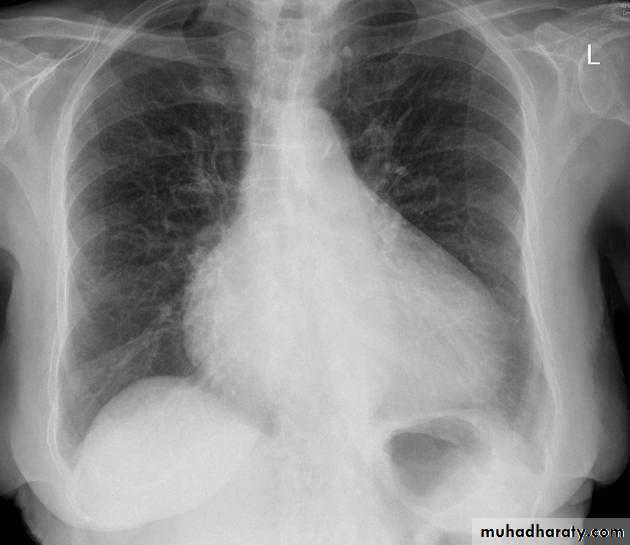

Tetralogy of Fallot (TOF) is one of the most common cyanotic congenital heart conditions and continues to be a major source of morbidity .

Tetralogy of Fallot is classically characterised by four features which are:

ventricular septal defect (VSD) 6

right ventricular outflow tract obstruction (RVOTO) due to:pulmonary artery stenosis

overriding aorta

right ventricular hypertrophy

Radiographic features

Plain film

Plain films may classically show :

1. "boot shaped" heart with an upturned cardiac apex due to right ventricular hypertrophy and concave pulmonary arterial segment.

2.Pulmonary oligaemia due to decreased pulmonary arterial flow.

3.Right sided aortic arch is seen in 25%.

"boot shaped" heart ( TOF )

TOF